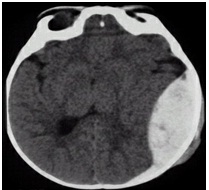

Decompressive craniectomy (DC) can be performed unilaterally or bilaterally and can be approached via temporal, frontal or circumferential excisions. The underlying dura may be opened or left intact. Due to the variety of methods used by both adult and pediatric neurosurgeons for this infrequent procedure the strength of research on results is lacking. Currently level III recommendations recommend employing DC in those with medically refractory intracranial hypertension or patients with neurologic deterioration and signs of herniation who have an intracranial lesion that can be evacuated. A craniectomy in which the bone flap is fully removed and a duraplasty performed are the recommended procedures. These recommendations are based on class III studies which found generally decreased ICP measurements with varying clinical outcomes. These studies had diverse indications for DC and operative methods thus limiting their widespread application [24].

Several retrospective studies have been performed analyzing the effect of DC on clinical outcomes. Unfortunately these studies also utilized varying indications and methods of approach and also contained few patients. Outcomes ranged from a “complete recovery” to “better than expected” and when used, quality of life questionnaires had mean scores of 4 of 5 [45][46][47]. Functional assessments found patients required minimal assistance or were fully independent [48]. Current formal recommendations are that outcomes may be improved in patients with DC [24].